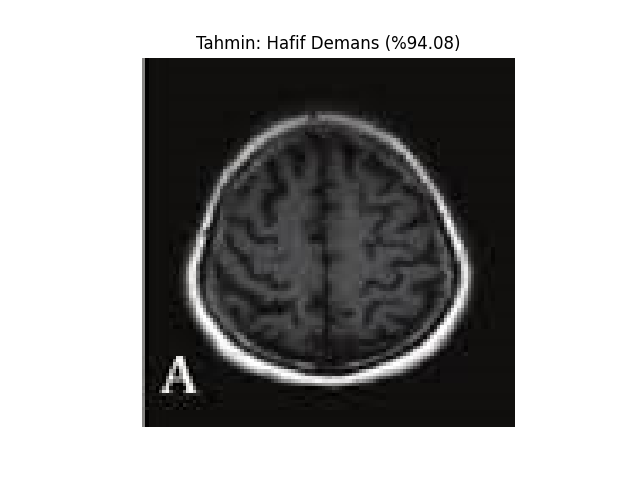

def show_image_with_prediction(image_path, prediction, confidence, class_names):

image = Image.open(image_path)

plt.imshow(image)

plt.title(f"Tahmin: {class_names[prediction]} (%{confidence * 100:.2f})")

plt.axis('off')

plt.show()

test_image_path = 'MRI/veya/fMRI/görüntüsü'

prediction, confidence = predict(test_image_path, model, transform)

print(f'Tahmin: {class_names[prediction]} (%{confidence * 100})')

show_image_with_prediction(test_image_path, prediction, confidence, class_names)Vbai Modelleri;